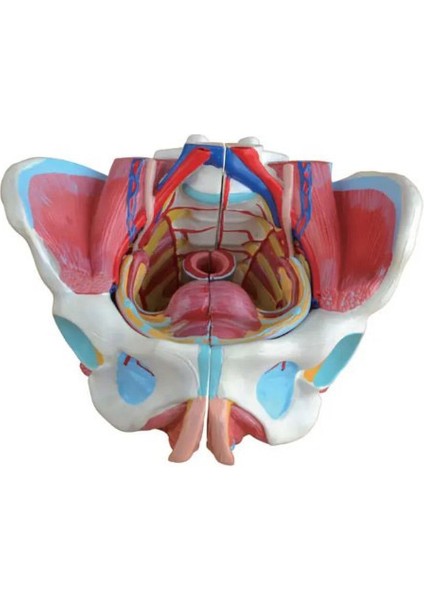

Kadın Pelvis Modeli - Pelvis Maketi

Bu model gerçeğe yakın renklerle boyanmıştır. Kemik pelvis yapısı içindeki tüm iç ve dış kadın organlarını, kan damarlarını, bağları, sinirleri ve kas yapılarını göstermektedir. Gerçek boyutlardadır.

Ölçüleri: 25x22x17cm